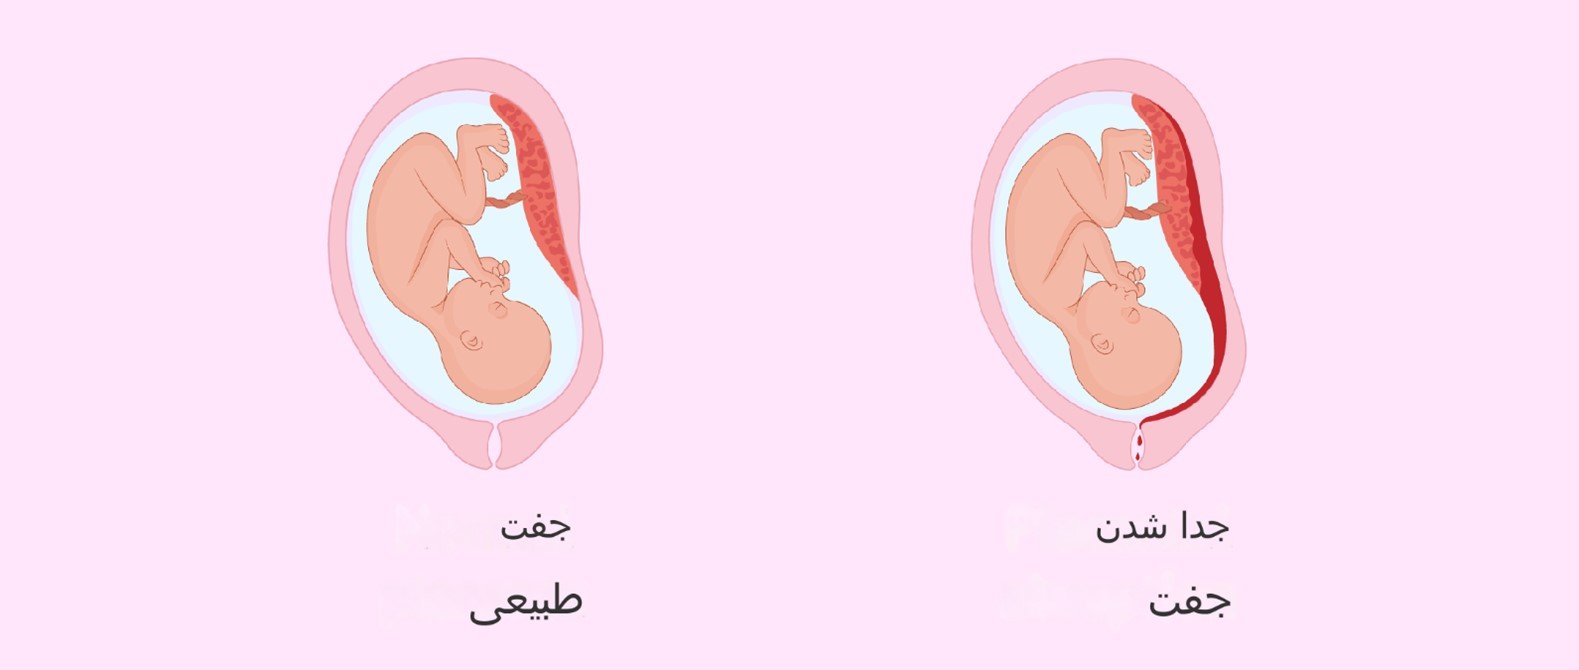

-جداشدگی جفت، دکولمان: در جداشدگی جفت یا دکولمان، جفت قبل یا در حین تولد از دیواره رحم جدا می شود. شایع ترین علائم و نشانه ها خونریزی واژینال و درد شکم یا کمر است. جدا شدن جفت اگر زود تشخیص داده نشود می تواند عوارض جدی ایجاد کند. ممکن است جنین اکسیژن کافی دریافت نکند و زن باردار مقدار زیادی خون از دست بدهد.

جدا شدن جفت یا دکولمان: وضعیتی که در آن جفت قبل از تولد جنین شروع به جدا شدن از رحم کرده است.